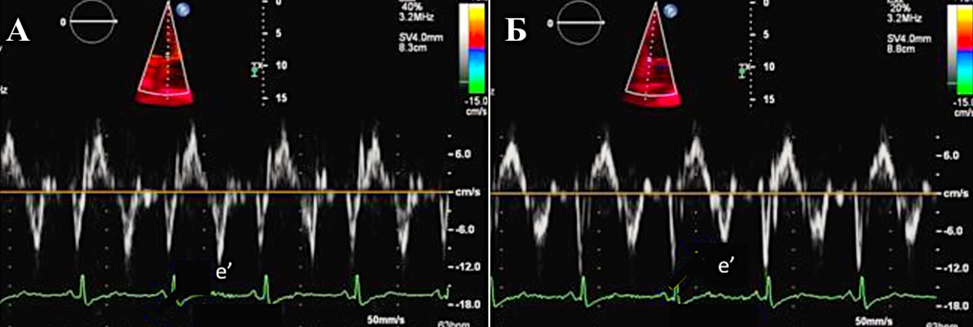

В диагностике констриктивного перикардита также может быть полезна тканевая допплерография, демонстрирующая так называемый феномен “annulus reversus”, заключающийся в том, что нормальная или повышенная ранняя диастолическая скорость движения медиальной части митрального кольца (медиальная е') оказывается выше, чем ранняя диастолическая скорость движения латеральной части фиброзного кольца (латеральная е’) (Приложение А3, рис. А3-2) [117].

Сочетание разнонаправленного смещения МЖП в зависимости от фаз дыхания с увеличением ранней диастолической скорости движения медиальной части митрального кольца (медиальная е') ≥9 см/сек имеет самую высокую диагностическую чувствительность (87%) и специфичность (91%) [118].

Допплер-ЭхоКГ позволяет определить парадокс кольца. Он заключается в том, что при относительном сохранении способности миокарда растягиваться в продольном направлении деформация продольной оси левого желудочка и продольная ранняя диастолическая скорость либо нормальные, либо, по мере прогрессирования констриктивного перикардита, увеличиваются. В то время как при рестриктивной кардиомиопатии или при заболеваниях миокарда происходит снижение этих показателей. При этом усредненная максимальная тканевая скорость раннего диастолического смещения септальной части митрального кольца выше латеральной (Приложение А3, рис. А3-5) [117, 123, 124–128]. Несмотря на высокую чувствительность и специфичность (95% и 96% соответственно), ограничение данного признака при диагностике будет проявляться в случае неоднородности поражения перикарда или при кальцификации кольца митрального клапана.